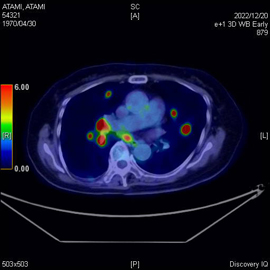

PET-CT検査とはPETとCTを同時に行える検査です。この検査の最大の利点はPET装置とCT装置を一体化することにより、PETの「機能画像」と、CTの「形態画像」を時間差や体位のズレなどがほぼない高精度な融合画像を作成できることです。癌の早期発見、転移・再発の有無、治療効果判定などに大変有効です。

当院のPET検査に使用される薬剤は18F-FDGといって、ブドウ糖に類似したFDGという物質に微量な放射線を出す放射性同位元素を結合させた薬剤です。がん細胞は正常な細胞より3~8倍多くのブドウ糖を取り込むという性質があり、それを利用してFDGの多く集まった部位を画像上で特定します。FDGはブドウ糖の類似体なので薬剤による副作用はほぼありません。

PET-CTの画像